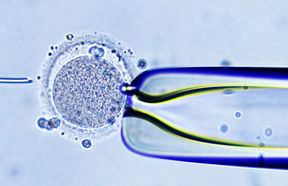

ń¼¼õĖĆõ╗ŻĶ»Ģń«ĪÕ®┤Õä┐’╝ÜĶ»Ģń«ĪÕ®┤Õä┐’╝łIVF- ET’╝ē